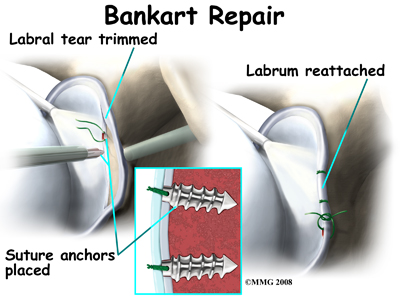

Once any degenerative tissue and bone spurs are removed, the torn ligaments that stabilize the shoulder are reattached to the bone around the socket of the shoulder, the glenoid. Special devices have been designed to reattach these ligaments. These devices are called suture anchors.

Suture anchors are special devices that have been designed to attach tissue to bone. In the past, many different ways were used to attach soft tissue (such as ligaments and tendons) to bone. The usual methods have included placing stitches through drill holes in the bone, special staples and screws with special washers – all designed to hold the tissue against the bone until healing occurred. Most of these techniques required larger incisions to be able to see what was going on and to get the hardware and soft tissue in the right location.

Today, suture anchors have simplified the process and created a much stronger way of attaching soft tissue to bone. These devices are small enough that the can be placed into the appropriate place in the bone through a small incision using the arthroscope. Most of these devices are made of either metal or a special plastic-like material that dissolves over time. This is the “anchor” portion of the device. The anchor is drilled into the bone where the surgeon wished to attach the soft tissue. Sutures are attached to the anchor and threaded through the soft tissue and tied down against the bone.